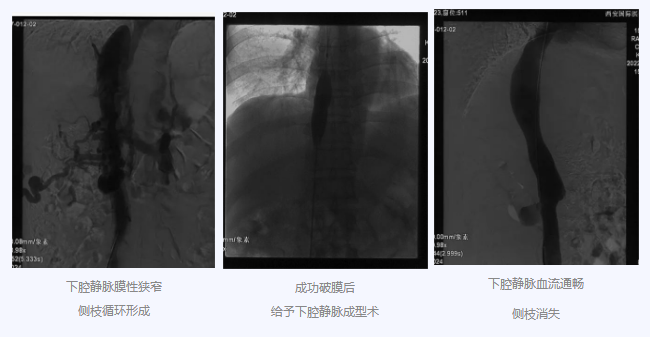

入院后,在韓國宏院長的安排下,臨床經(jīng)驗豐富的醫(yī)師給老謝做了B超、CT 等檢查,結果顯示:三支肝靜脈近心端閉塞,肝內側枝循環(huán)形成,下腔靜脈近心房入口處隔膜樣狹窄,隨后的DSA血管造影也證實:下腔靜脈狹窄,且有側枝形成,最終確診困擾老謝20年的疾病為混合型布加綜合征,是一種罕見病。

明確診斷后,韓院長帶領團隊縝密分析老謝的病情,為其制定最佳的治療方案,考慮到老謝的根本病因是下腔靜脈阻塞,介入手術成為首選治療方法,通過微創(chuàng)介入手術,可準確打通患者的閉塞血管,癥狀迅速緩解。做好充分術前準備后,為患者行“下腔靜脈成型術”,精準定位快速貫通,閉塞的下腔靜脈順利開通,手術圓滿完成。